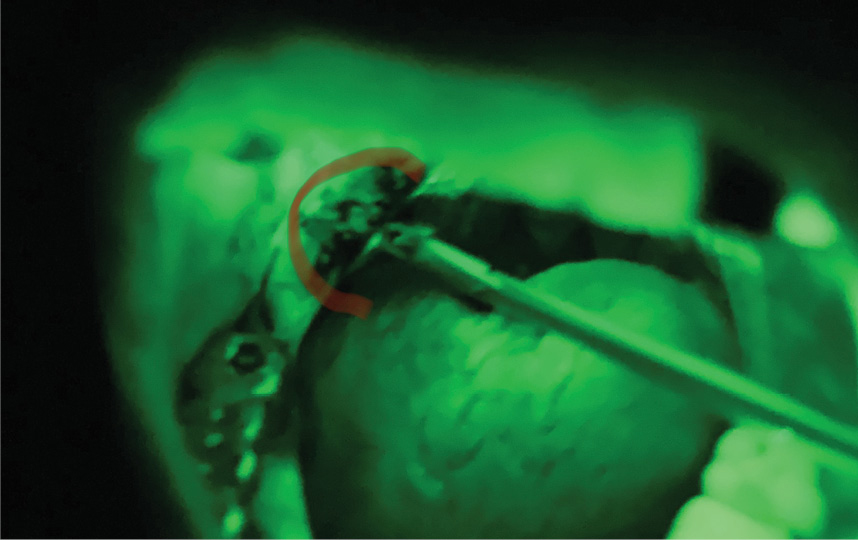

In the control group, IB with tissue removal from the pathological focus for histological examination was performed using otorhinolaryngological conchotomes at random under direct vision from the surface and along the edge of the pathological formations (Figure 1). In the main group, AFS was performed using an AFS-400 device and glasses with a green light filter. When using the lamp, precancer and cancer signs were assessed on a light scale, where a dark glow (dark spot effect) indicated the precancer and cancer foci.

Рисунок 1. Инцизионная биопсия опухоли слизистой щеки под контролем глаза с использованием оториноларингологического конхотома.

Figure 1. Incisional biopsy of cheek mucosa tumor under eye-control using an otorhinolaryngologic conchotome.

In the main group, biopsy was performed using otorhinolaryngological conchotomes under AFS control, and tissue samples were obtained from sites of pathological glow (dark spot) (Figure 2).

Рисунок 2. Инцизионная биопсия опухоли слизистой ретромолярного пространства с использованием лампы «АФС-400», очков с зеленым светофильтром и оториноларингологических конхотомов.

Figure 2. Incision biopsy of retromolar mucosa tumor using "APS-400" lamp, glasses with green light filter and otorhinolaryngological conchotomes.